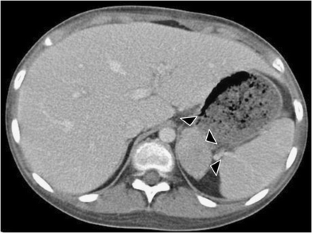

Adrenocortical oncocytomas are rarely reported, occur almost exclusively in adults, and are mostly nonfunctional. Here, we report an interleukin-6 (IL-6)-producing adrenocortical oncocytoma in an 11-year-old girl presenting with fever, body weight loss, and increased levels of inflammatory markers and serum IL-6. Imaging studies revealed a 4-cm mass in the left adrenal gland. After complete resection, laboratory findings returned to normal. Histology was consistent with adrenocortical oncocytoma, and the tumor cells stained positive for IL-6. Conclusion: IL-6-producing adrenocortical oncocytoma should be included in the differential diagnosis and imaging studies should be performed in patients presenting with persistent fever of unknown origin and high levels of inflammatory markers.